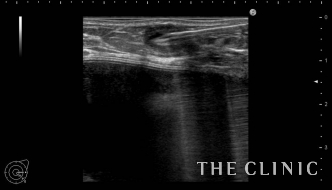

吸引後、エコーにてしこりの消失を確認しました。 ヒアルロン酸のしこりはエコー下に行えば 、安全に確実に治療することが可能です。